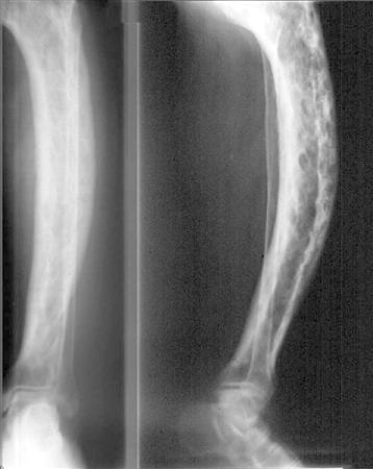

Bệnh Paget xương: chẩn đoán và điều trị

22/11/2018

Bài viết cung cấp thông tin chung về chẩn đoán và điều trị bệnh Paget xương

Bệnh Paget xương: những điều cần biết

Bệnh Paget xương là một bệnh mạn tính với việc phân hủy và hình thành mô xương quá mức, có thể dẫn đến phì đại, suy yếu và gãy xương, cũng như gây đau và viêm ở các khớp gần xương bị ảnh hưởng.